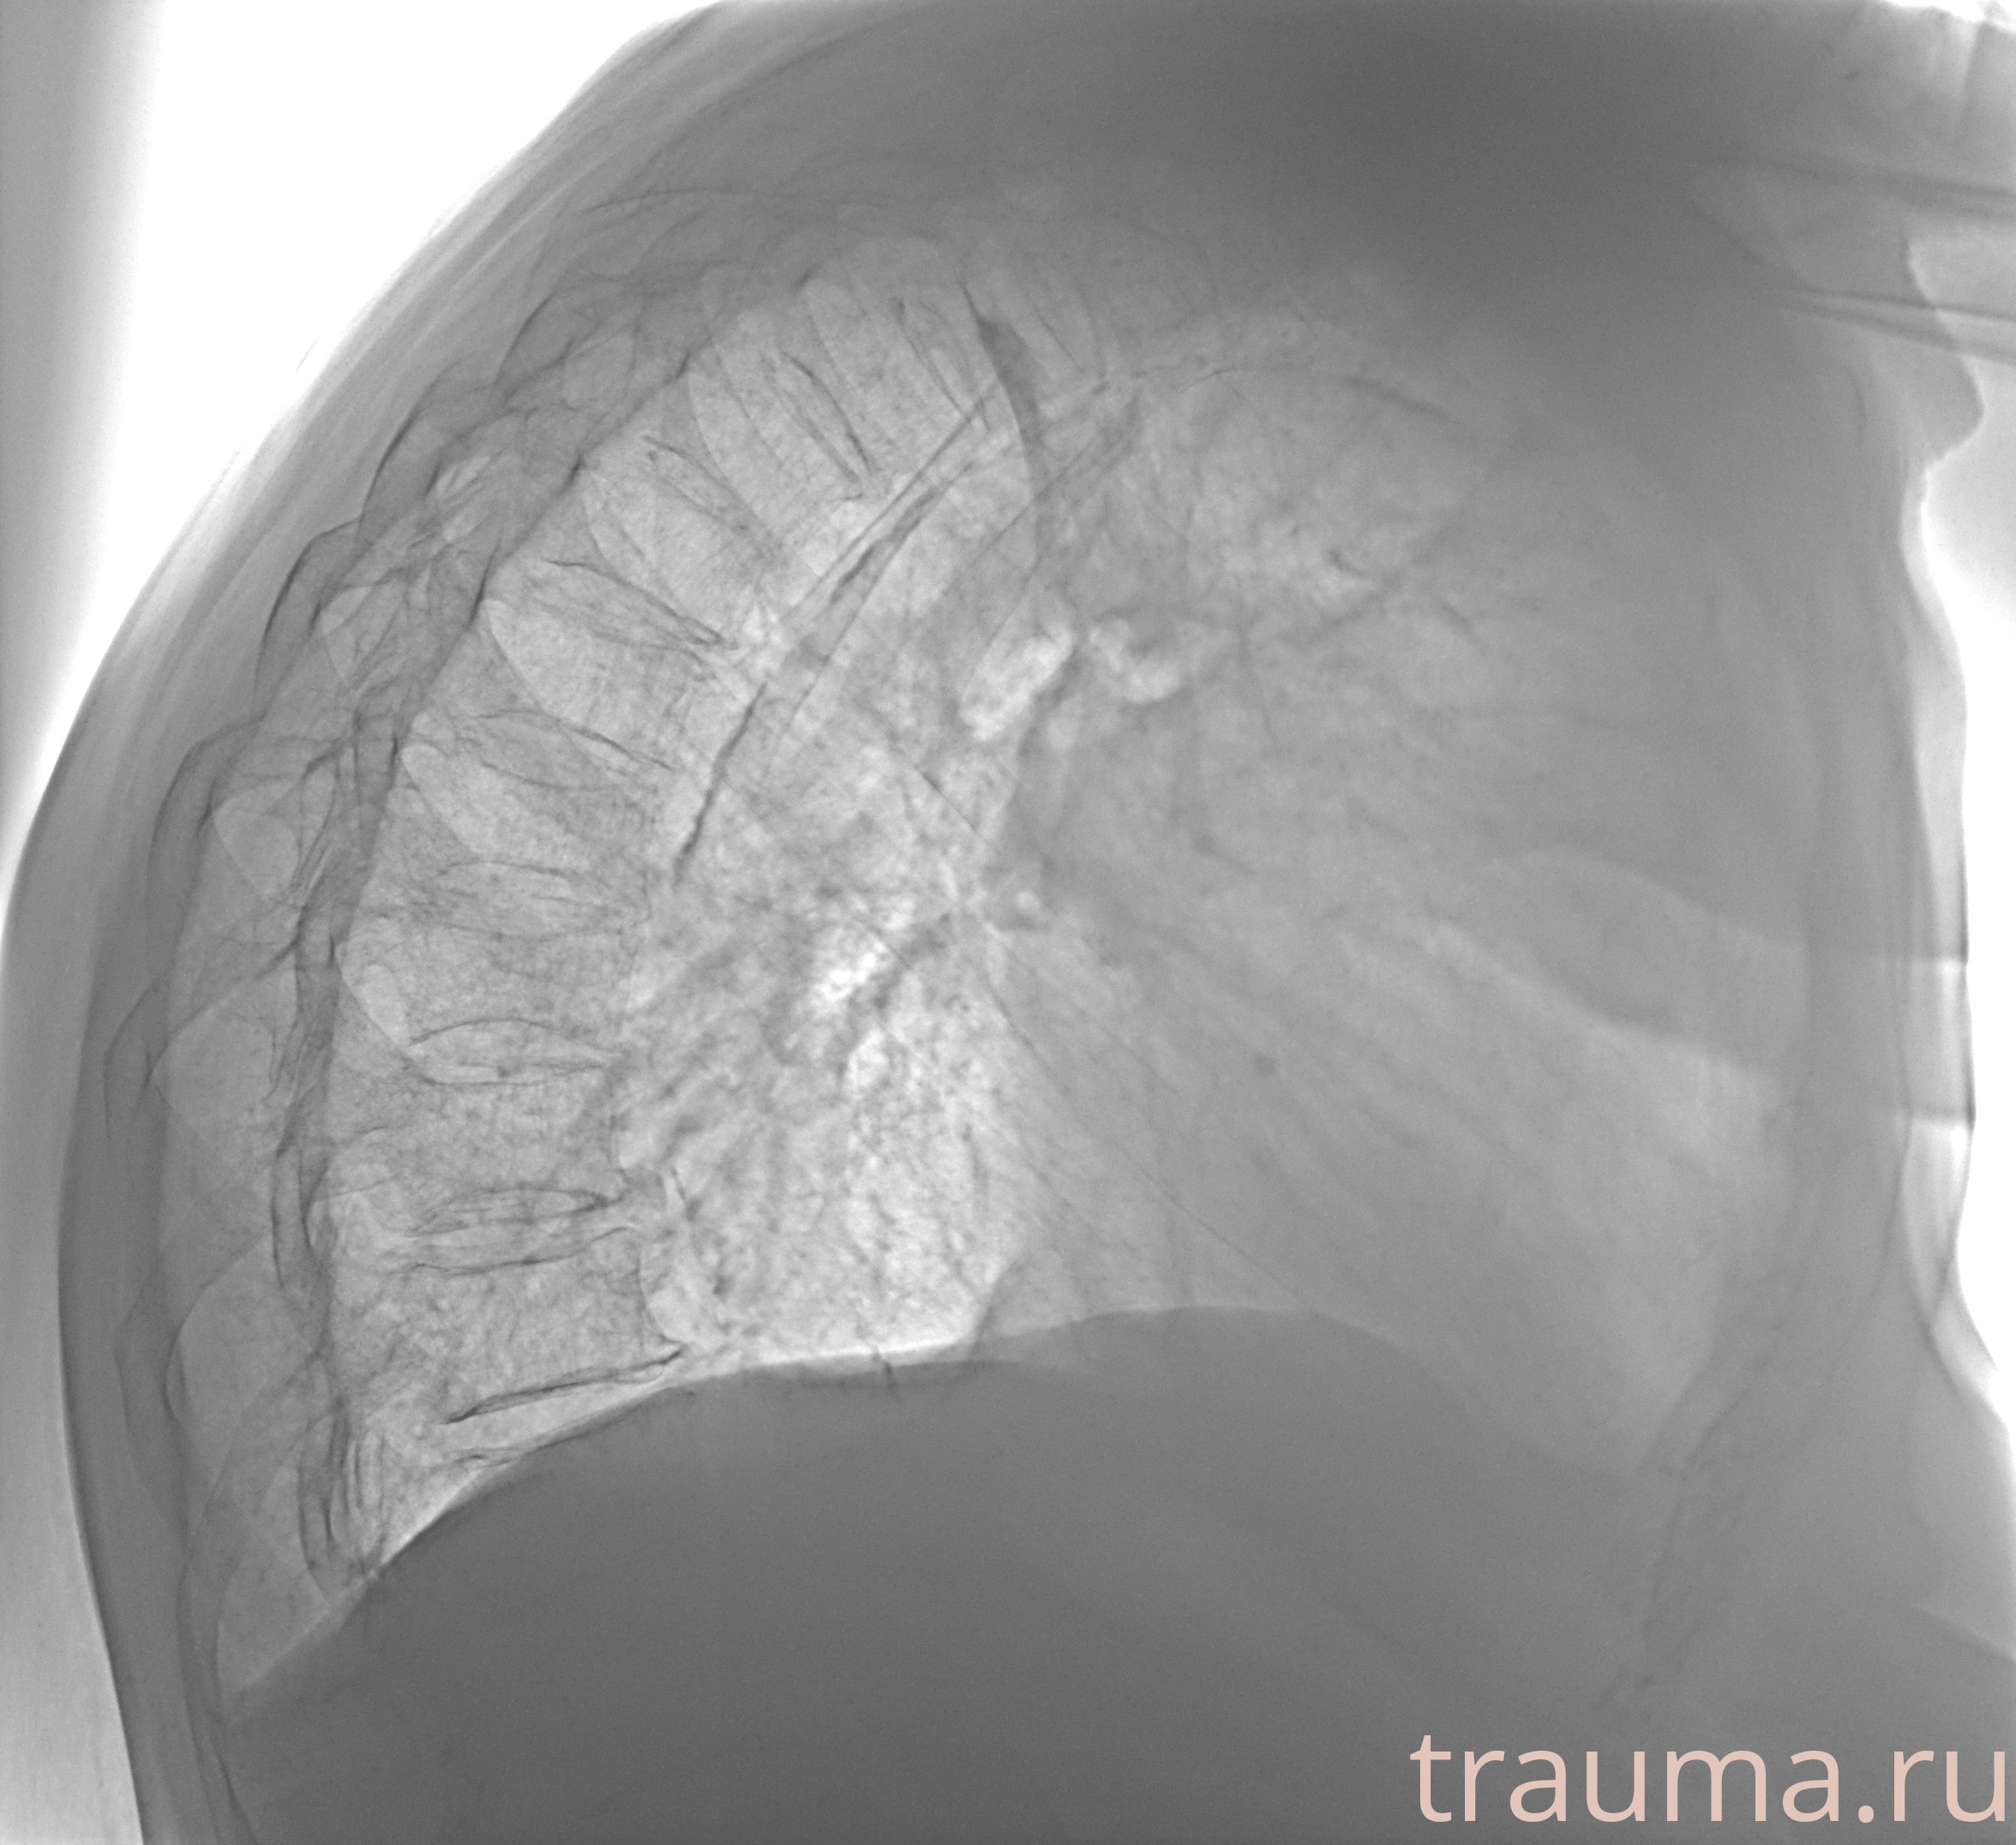

Рентгенограммы

Рентген на дому: по вашему адресу приезжает врач-рентгенолог, травматолог-ортопед с мобильным рентгеновским аппаратом, проводит диагностику травмы или заболевания, делает необходимые рентгенограммы, дает рекомендации по дальнейшему лечению. Получить качественные снимки в домашних условиях возможно благодаря уникальной методике, разработанной МосРентген Центром для института  Склифосовского

Яркость: 1   Контраст: 1   Инвертировать: 0 Увеличение: 1

Перетаскивайте мышь вверх/вниз для контраста, влево/право для яркости. Прокрутка колесом изменяет масштаб. Нажмите Сбросить для возврата к исходному изображению. При увеличении держите мышь в той области, которую хотите рассмотреть.